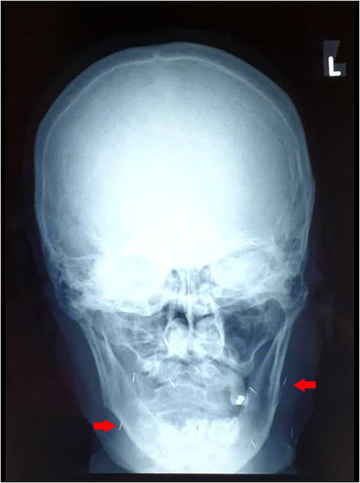

Внешне их никак не видно. и так как используются благородные металлы, вреда организму не бывает, амулеты можно увидеть только на рентгенограмме.

Полюбоваться, как это выглядит, вы можете на рентегнограммах